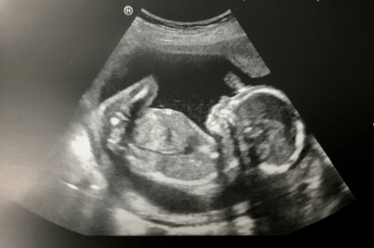

38 weeks pregnant… Hurry up baby!!!

Now I’ve hit the pregnancy wall! As of three days ago I look like a duck waddling around, stairs have become my nemesis, and my appetite has increased by at least double. To be honest I think this baby needs to diet… at this rate he’s gonna come out looking like a Weetabix (my snack of choice).